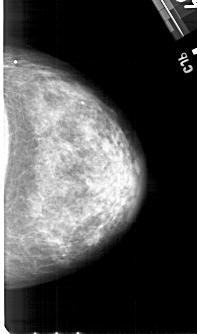

A_1427_1.LEFT_MLO

LEFT_MLO LINES 5356 PIXELS_PER_LINE 2941 BITS_PER_PIXEL 12 RESOLUTION 43.5 OVERLAY